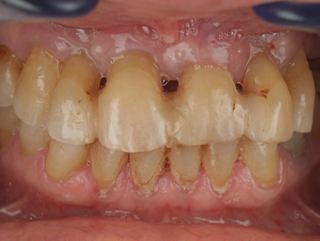

Facially driven Smilecloud design with a focus on preserving tissue and bone. Planned in Smile in a Box and executed with the iGuide protocol; shared pin positions align the drill and prosthetic guides for chairside pickup of the pre-designed provisional. Day-5 follow-up shows the screw-retained provisional in place.

• Day 5 post-op: screw-retained provisional in place.